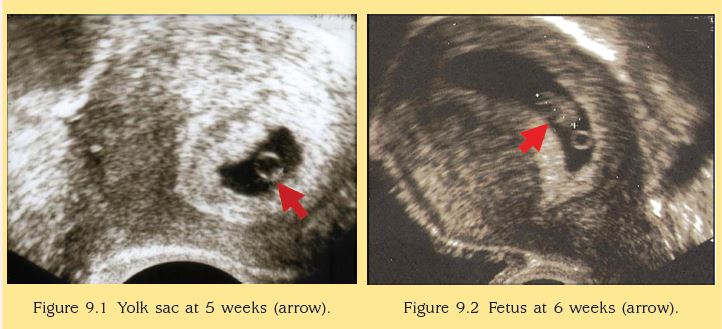

6 Weeks Pregnant Baby Development Symptoms Signs Week by Week Very well made.

6 Weeks Pregnant Growing What To Expect What To Do Very well made.

Watch Your Baby s Growth at Week 6 Very well made.